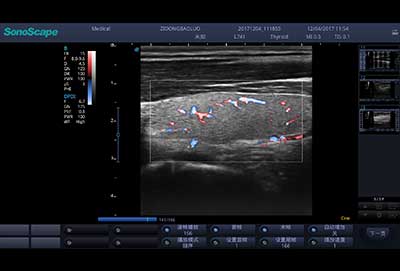

血管内中膜自动测量